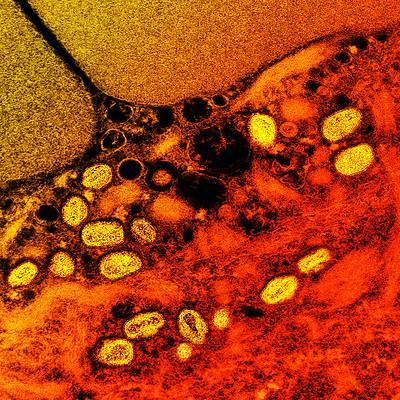

Spain reports first known human-to-human #mpox clade 1b transmission outside Africa Previous cases in Europe had travel ties to endemic regions. https://t.co/5Zztp2xXQg Photo: NIAID / Flickr cc